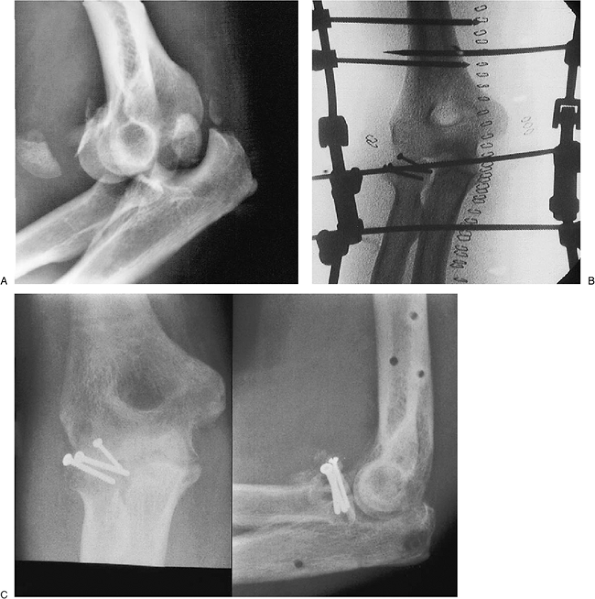

a type III radial head fracture. The subluxation persisted for 3 weeks

before treatment (Fig. 8-26A). The fracture was managed

with osteosynthesis (Fig. 8-26B). The construct was protected or “neutralized” by the DJD II (Fig. 8-26C).

Figure 8-26. Complex dislocation with a Mason III radial head fracture dislocation (A).

The fracture is fixed with intrafragment compression osteosynthesis and the construct is stabilized by the DJD II external fixator (B). The fracture healed with an arc of 20 to 140 degrees of flexion and no pain (C). |